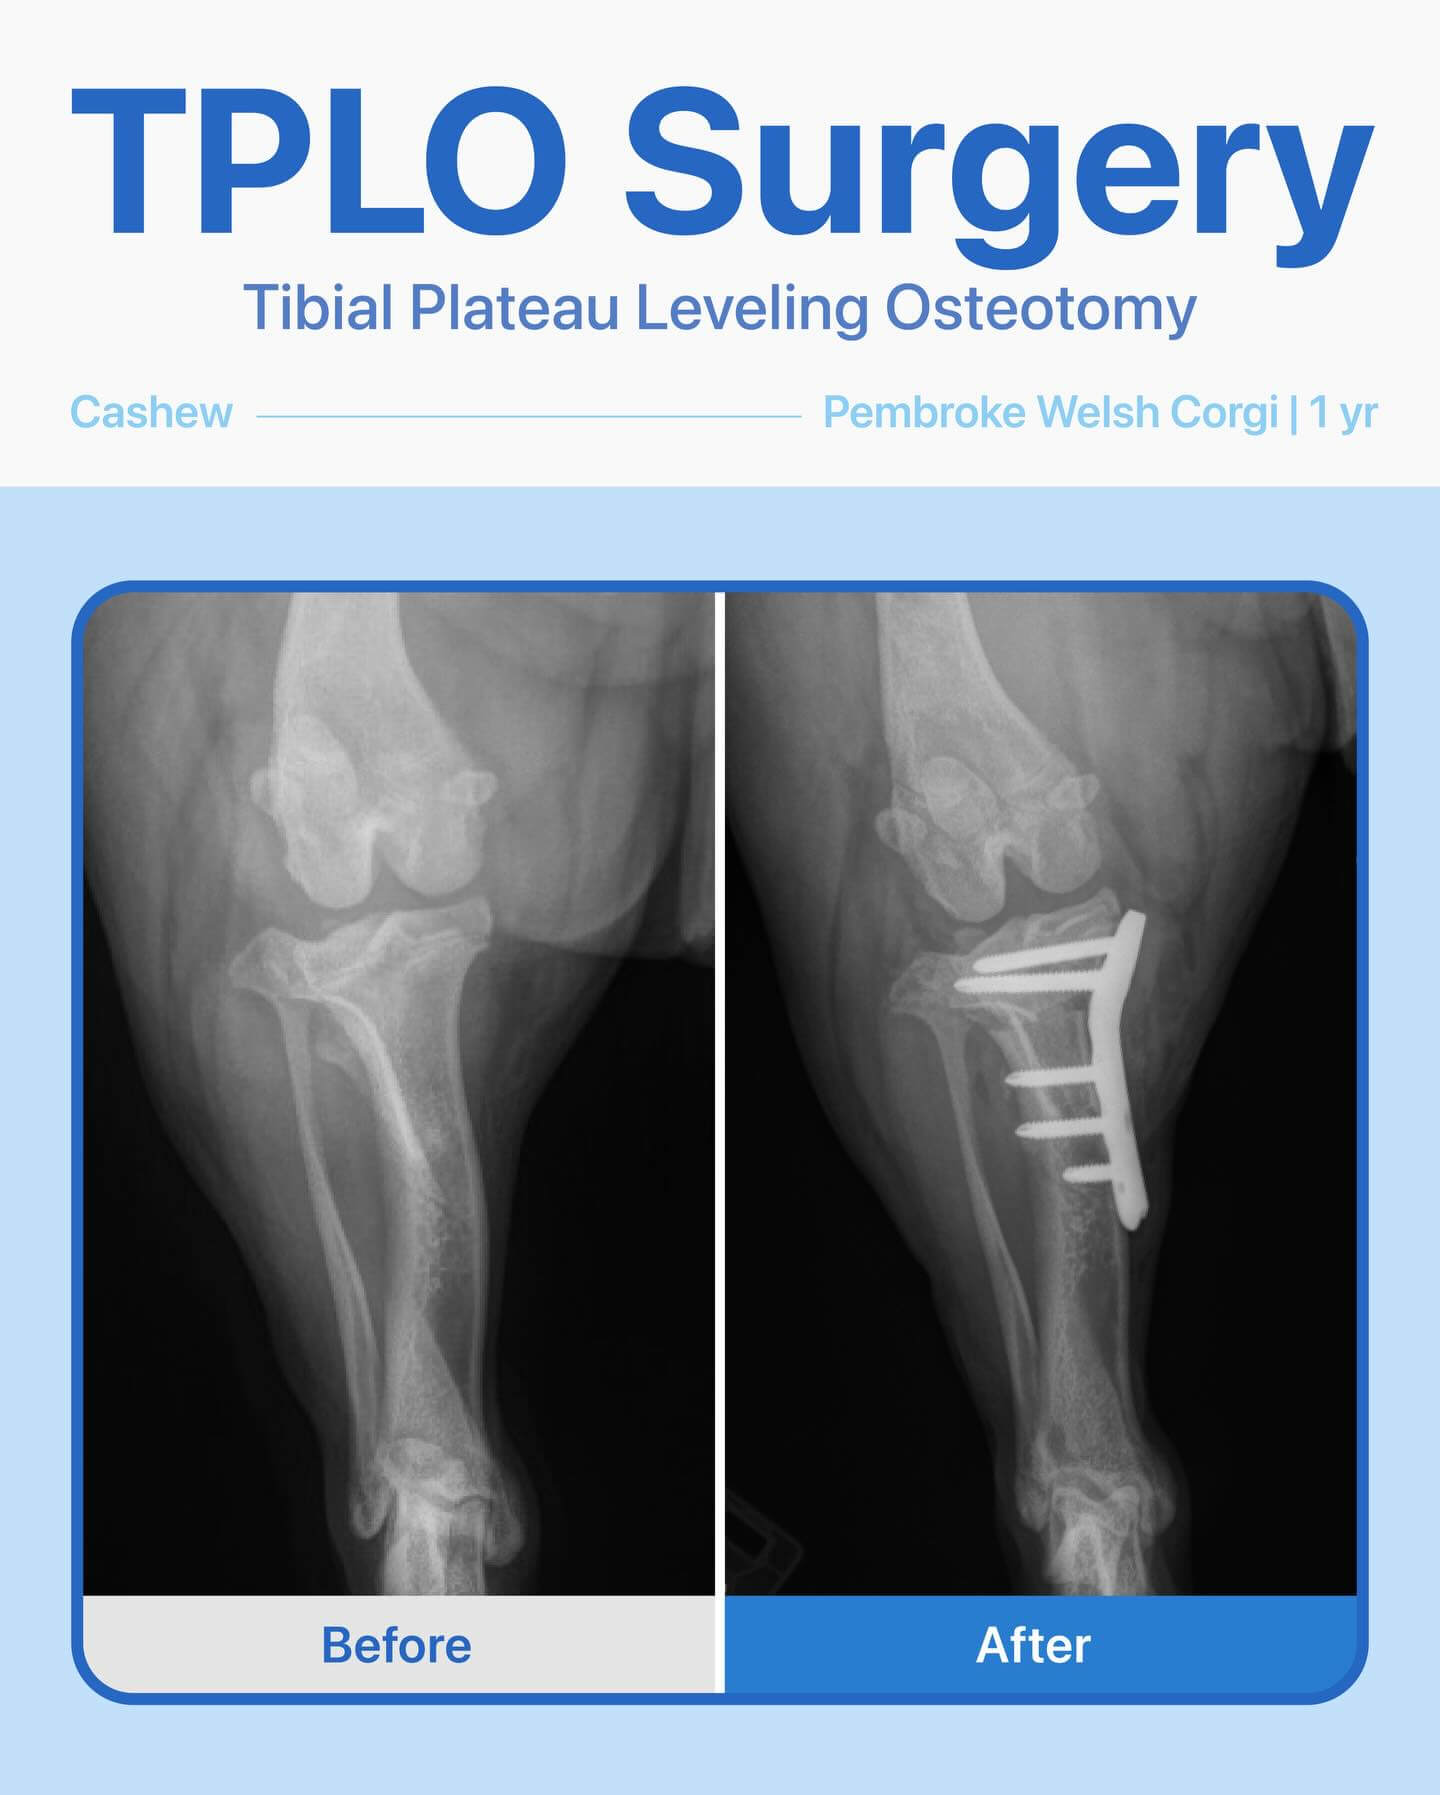

After radiographs and a thorough exam, we discovered he had a cruciate ligament tear and would need TPLO surgery to get him back on his feet. Before the procedure, we ran blood tests to make sure he was healthy—and everything looked great.

The surgery went smoothly, and Cashew has been healing beautifully! He’s a brave little pup, and it’s been amazing to watch him recover and get back to his playful self.